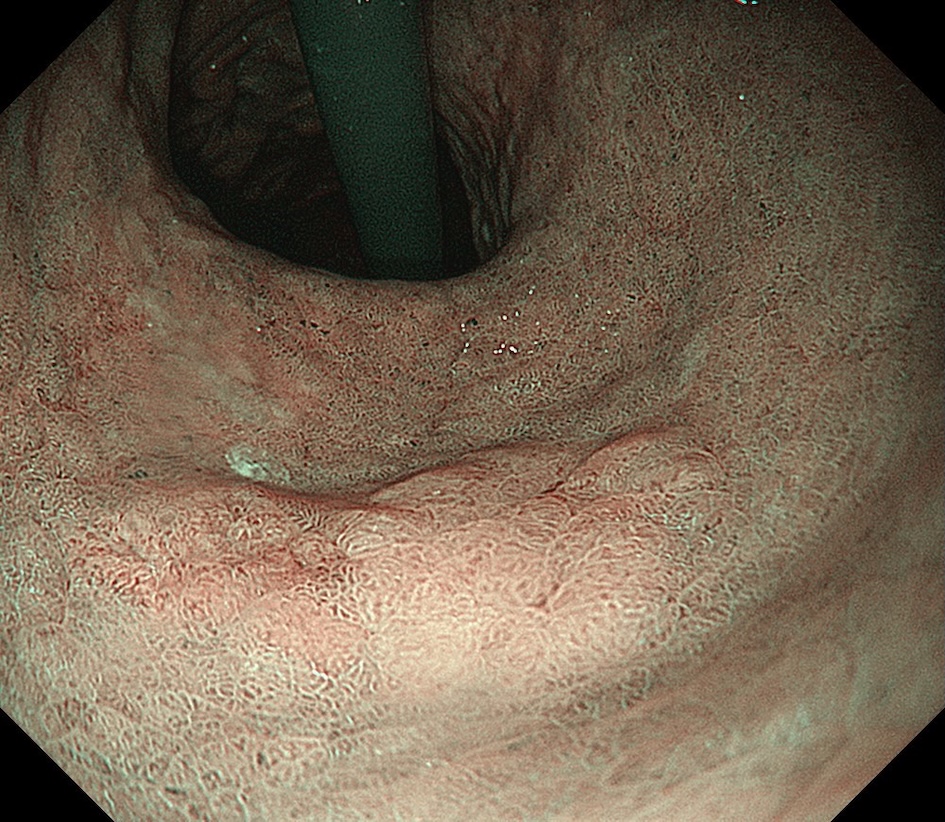

• 白色光観察①(中遠景)

強調設定:B8

図1

白色光観察:体下部小彎に約15mm大の褪色調を呈する平坦な病変を認める。病変辺縁は一部で不明瞭である。